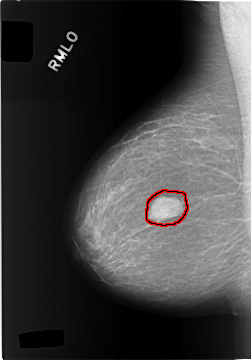

C_0305_1.RIGHT_MLO

FILE: C_0305_1.RIGHT_MLO.OVERLAY

TOTAL_ABNORMALITIES 1

ABNORMALITY 1

LESION_TYPE MASS SHAPE LOBULATED MARGINS CIRCUMSCRIBED

ASSESSMENT 4

SUBTLETY 5

PATHOLOGY BENIGN

TOTAL_OUTLINES 1

BOUNDARY